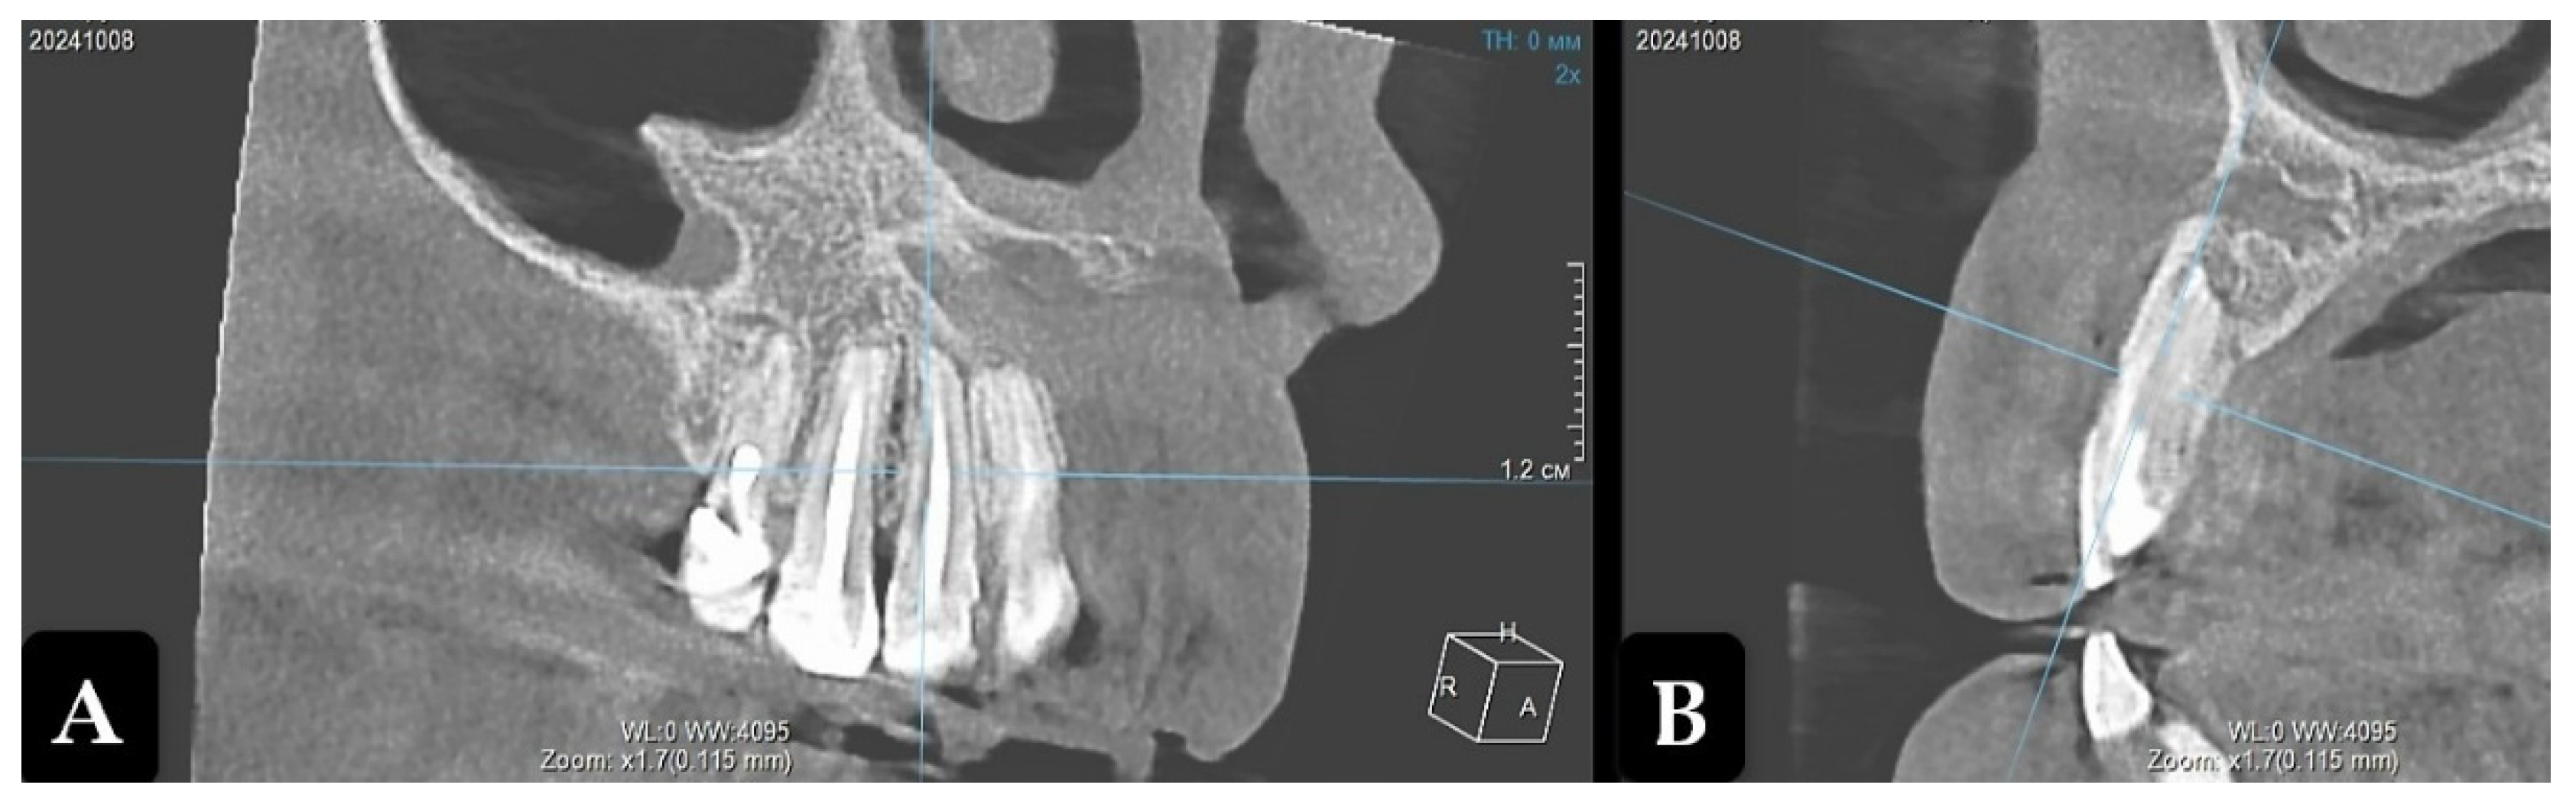

Cone-beam computed tomography (CBCT) revealed osteolytic lesion with clear contours and a well-defined sclerotic margins of varying thickness. It extended 17 mm in the vestibulo-oral direction to the border of the maxillary sinus, significantly pushing it aside, and 22 mm along the alveolar bone in the mesiodistal direction from tooth 1.3 to 2.1. The endodontically untreated apical parts of the teeth roots 1.3, 1.2, 1.1 and 2.1 protruded into the periradicular lesion. Due to the preservation of sufficient bone thickness on the vestibular side, root divergence was not observed (Figure 1).

Figure 1. Cone-beam computed tomography. Maxillary radicular cyst before treatment (projection of tooth 12). A: Frontal projection; B: Sagittal projection.